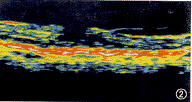

图3   患者男, 72岁, 右眼视力减退半年, 视力0.1。OCT示黄斑神经上皮全层缺失, 裂孔周围视网膜增厚, 并可见微囊样改变